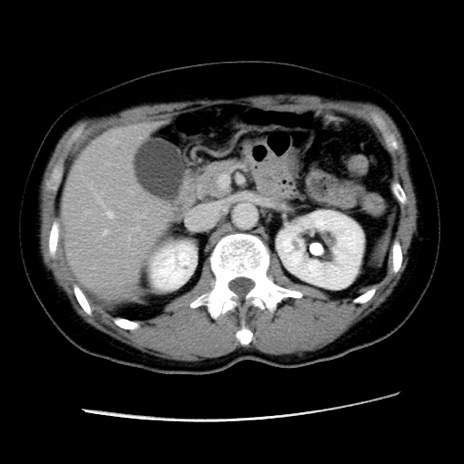

症例10(横断像)

【症例】 50歳代女性

【主訴】 腹痛

【現病歴】前日生レバーを食べた。今朝に排便あり。 昼前に突然発症の腹痛を生じ、当院救急外来を受診した。

【既往歴】 子宮筋腫にてで子宮全摘後

【身体所見】 意識清明、腹部:平坦、軟、下腹部やや左を中心に圧痛・反跳痛あり、筋性防御あり

【データ】WBC 7800、CRP 0.07